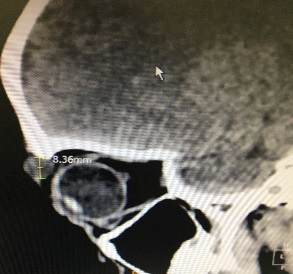

Any tumour mass can occur within the bony socket of the eye. It may occur as a primary tumour or secondary tumour (metastatic disease). It is also essential to know the difference between a benign and malignant tumour. After discussing the symptoms and signs, a detailed clinical examination and some clinical tests, Dr Nazila will order for an imaging such as CT scan or MRI and advise for surgery.

Thyroid eye disease can be as a result of high, normal or low thyroid hormone levels of patients affected with thyroid disease. Depending on the severity of thyroid eye disease, management will be tailored accordingly. Most patients will only require medical treatment but a small proportion will require surgical intervention to correct the appearance and functionality of the eye. In acute cases where medical treatment is refractory, surgical orbital decompression is the only way to salvage a patient's vision. At other times, when thyroid disease has achieved stability, the bulging eye appearance can be alleviated by orbital decompression. Squint from thyroid eye disease can be addressed surgically and eyelid surgery can be performed.